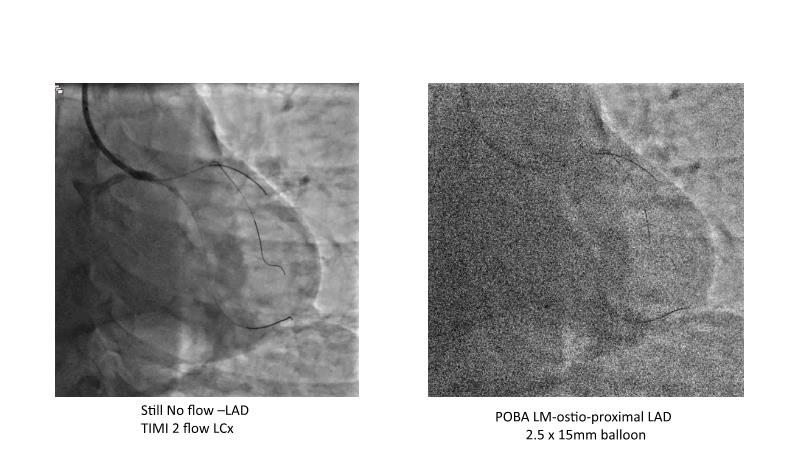

This session is recommended for you if you are seeking insights into the advantages of using IVUS imaging over visual assessment for better outcomes in left main bifurcation procedures. Discuss with experts the benefits of using RotaCUT in lesion preparation for left main bifurcation and explore the impact of high radial strength stents on the procedure's success.

• To know how a high radial strength stent can make a difference in left main bifurcation